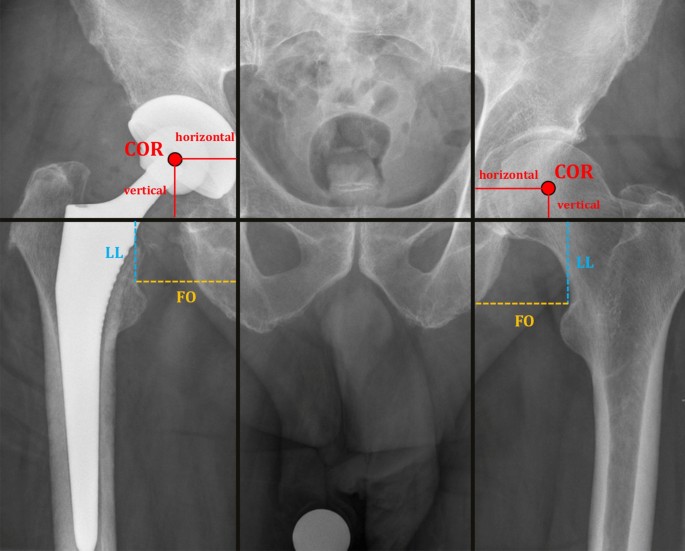

Standardized radiographs of the pelvis with a reference ball of 25 mm in anteroposterior direction were analyzed. Each radiographic image was centered on the pubic symphysis (equal size of the obturator foramens) and included both proximal femora. For each patient four different radiographic parameters (leg length (LL), femoral offset (FO), horizontal and vertical acetabular center of rotation distance (hCORD, vCORD)) were measured [in mm] in the same manner as previously published49 at four different stages during PJI treatment (Fig. 1). The radiographic parameters after pTHA and reTHA were evaluated on the first postoperative standardized radiographs. The initial pre-replacement status of the hip was recorded before pTHA and the RA parameters of the hip were determined on the radiographs immediately before reTHA. The measurements were performed on high-resolution monitors with diagnostic PACS (Picture Archiving and Communication System, Centricity PACS, General Electric Company Healthcare Systems) by two independent observers who were blinded to the other results.

Standardized radiographs of the pelvis demonstrating the technique for measurement of the different radiographic parameters (leg length (LL), femoral offset (FO), horizontal and vertical acetabular center of rotation distance (hCORD, vCORD)) during PJI treatment [in mm]. LL (blue line) was measured as the length between the interteardrop line and the lesser trochanter. FO (yellow line) was measured as the length between the teardrop and the lesser trochanter. The vCORD and hCORD (red lines) were measured as the length between the teardrop and the center of rotation (COR).